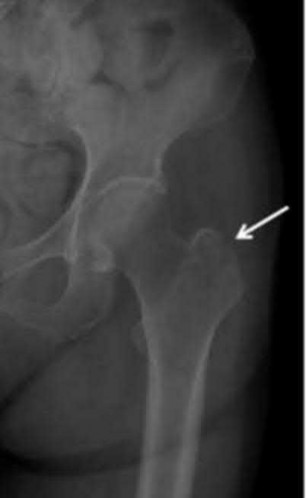

Question 10:

A 35-year-old male sustains a vertically oriented (Pauwels type III) basicervical femoral neck fracture. Which of the following fixation constructs offers the highest biomechanical stability for this specific fracture pattern?

Correct Answer: Sliding hip screw with an anti-rotation screw

Explanation:

Vertical fracture patterns (Pauwels III) experience high shear forces. A sliding hip screw (SHS) provides better resistance to vertical shear compared to cancellous screws. The addition of an anti-rotation (derotational) screw superior to the SHS provides optimal stability.